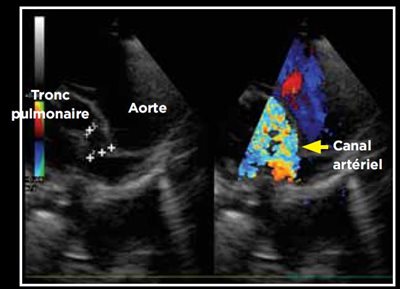

Photo 6 - Détermination du sens du flux en mode Doppler couleur: shunt gauche-droit avec des turbulences importantes dans le tronc pulmonaire. Mesure simultanée des dimensions du canal en mode bidimensionnel.

Le canal artériel est visualisé dans 96 % des cas en mode bidimensionnel ou en mode Doppler couleur sur une coupe petit axe transaortique par abord parasternal droit (Photo 1), sur une coupe petit axe par abord parasternal crânial gauche (Photo 2), ou plus facilement sur une coupe longitudinale des gros vaisseaux (aorte et tronc pulmonaire) par abord parasternal crânial et dorsal gauche (Photo 3).

La mesure de la taille du canal est réalisée en mode bidimensionnel ou en mode Doppler couleur, après identification. Les deux modes de mesures sont valables, la mesure en mode bidimensionnel étant la plus précise.

Du fait du différentiel de pression entre aorte et tronc pulmonaire, le shunt est le plus souvent gauche-droit. Ce shunt est visible en mode Doppler couleur (Photo 6), et mesurable en mode continu (Photo 7).